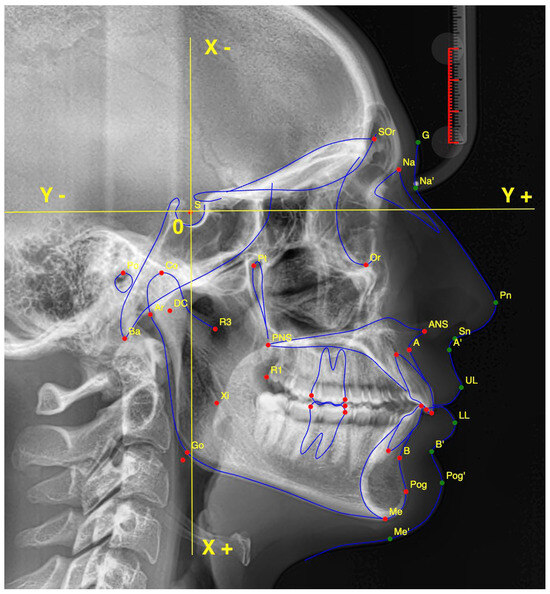

2.1. Cephalometric Landmarks

- Point (A);

- Anterior Nasal Spine (ANS);

- Articulare (Ar);

- Point (B);

- Gnathion (Gn);

- Gonion (Go);

- Lower Incisal Tip (L1);

- Lower Lip (LL);

- Menton (Me);

- Nasion (NA);

- Soft Tissue Pogonion (ST-Pog);

- Orbitale (Or);

- Posterior Nasal Spine (PNS);

- Porion (Po);

- Pogonion (Pog);

- Subnasale (SN);

- Upper Incisal Tip (U1);

- Upper Lip (UL).